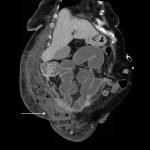

Significant findings:

Computed tomography (CT) of the abdominal and pelvis with intravenous (IV) contrast revealed inflammatory changes, including gas and fluid collections within the ventral abdominal wall extending to the vulva, consistent with a necrotizing soft tissue infection.